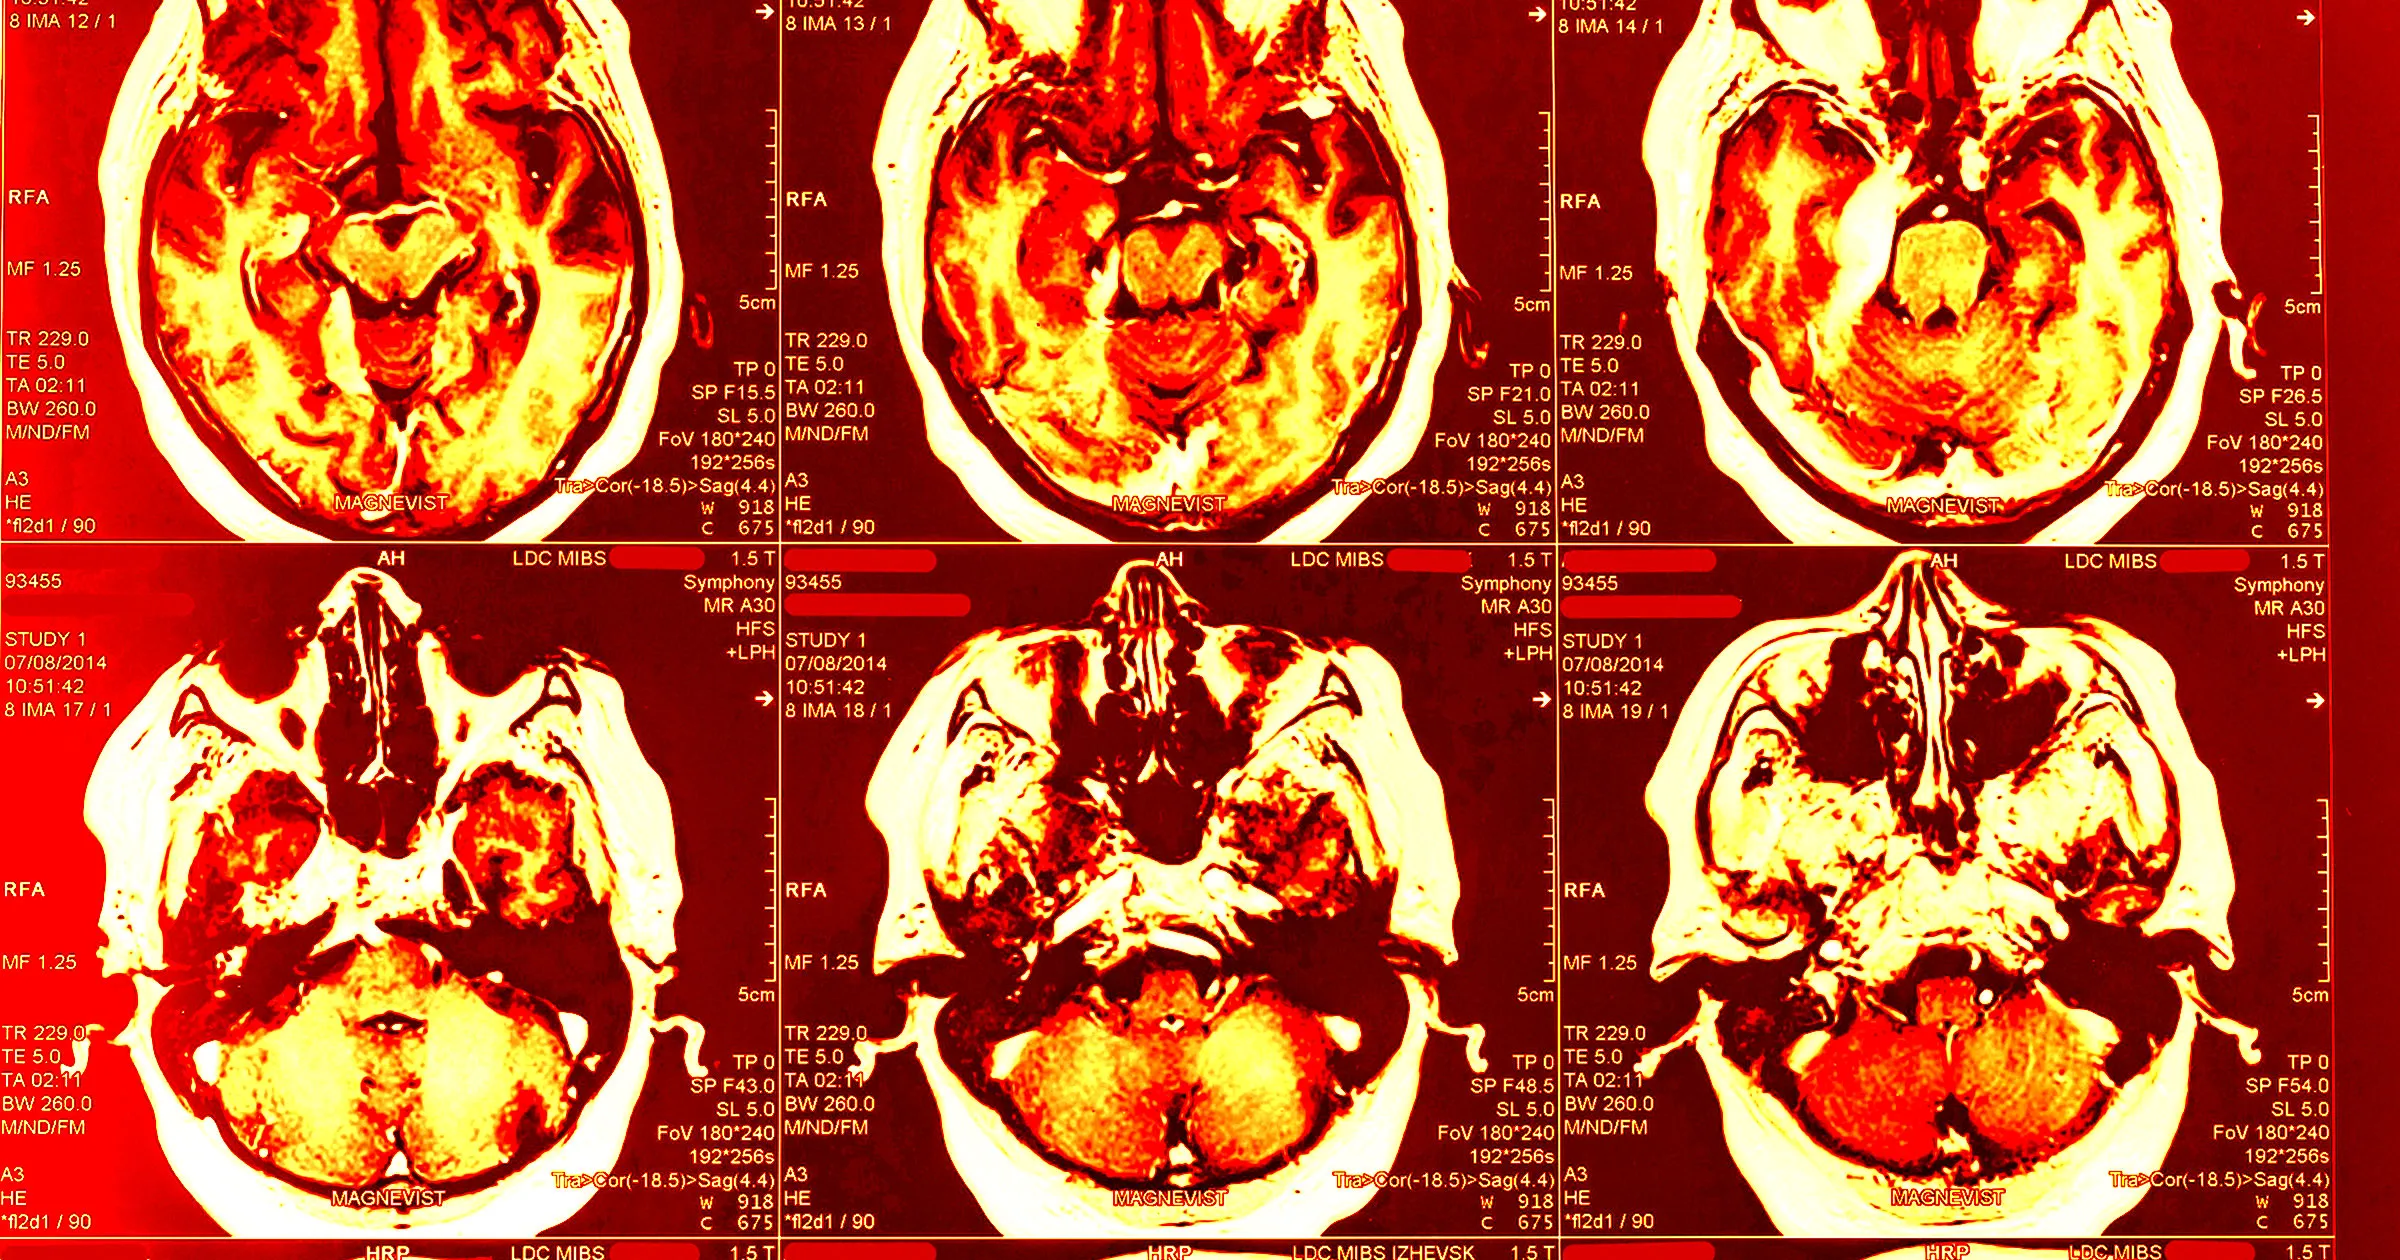

Severe CTE Linked to Dementia Risk, NIH Study Finds

An NIH-funded study of 614 donated brains with known repetitive head impacts shows severe CTE (stages III/IV) is strongly linked to dementia risk (stage IV ~4.5x higher); milder CTE (stages I-II) shows no association with dementia, mood changes, or functional decline, helping clarify CTE's role in neurodegeneration.